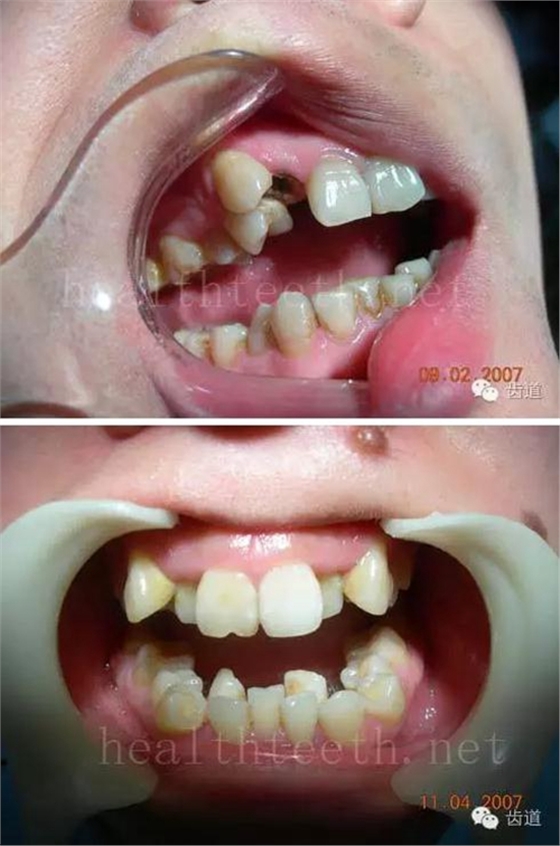

因?yàn)楸旧聿桓阏衬げ?,收集到的病例有限,大多是同事收?/span> 頰粘膜扁平苔蘚 舌粘膜扁平苔蘚 舌緣創(chuàng)傷性潰瘍 長(zhǎng)期戴活動(dòng)義齒不當(dāng)或是戴不良修復(fù)義齒造成的口腔粘膜潰瘍,應(yīng)該引起高度警惕,因?yàn)檫@種潰瘍?nèi)菀装┳?/span> 黑毛舌 舌息肉,該患者同時(shí)伴有胃、食管息肉,后來(lái)看內(nèi)科了,具體情況不詳 四、孩子的牙齒問(wèn)題 乳牙未退,牙根穿出牙齦對(duì)上唇粘膜造成刺激 乳牙滯留,也是孩子在退牙過(guò)程中最容易遇到的問(wèn)題 五、牙齒發(fā)育上的問(wèn)題 變色牙 氟斑牙 釉質(zhì)發(fā)育不全 四環(huán)素牙 牙神經(jīng)治療后的牙齒變色 10歲孩子剛剛萌出的牙齒變色 2、埋伏牙 左上乳3滯留,恒3未見萌出,曲面斷層片顯示牙齒埋伏 通過(guò)CT片確定埋伏牙齒具體的位置,顯示距離左側(cè)上頜竇很近,偏唇側(cè),這為手術(shù)定位提供了方便 手術(shù)中切斷、完整拔出,未損傷上頜竇 其他埋伏牙 3、多生牙 病例1 病例2 病例3,同時(shí)多生兩顆牙齒 4、各種畸形牙 畸形過(guò)小牙 融合牙:恒牙和乳牙都可以發(fā)生融合的情況(兩顆牙齒長(zhǎng)在了一起) 畸形中央尖:在牙齒的中央,兩個(gè)牙尖之間又多長(zhǎng)出一個(gè)牙尖,由于進(jìn)食的磨耗很容易造成磨穿,神經(jīng)就會(huì)與外界相通,出現(xiàn)牙髓炎的癥狀 六、牙齒的外傷 牙冠折斷 牙根折斷 烤瓷牙打樁修復(fù)后牙根折斷 外傷后牙齒的全脫位,應(yīng)該保留牙齒盡早做再植手術(shù) 七、牙齒的慢性損傷 牙頸部楔狀缺損 牙冠劈裂及完整拔除后的情況 牙根縱裂及拔除后的情況 牙隱裂,牙齒表面有肉眼看不到的裂紋,細(xì)菌通過(guò)其進(jìn)入牙髓,容易出現(xiàn)牙髓炎癥狀,嚴(yán)重可以造成牙齒的劈裂 這是一位來(lái)中國(guó)學(xué)習(xí)的俄羅斯大學(xué)生的牙齒,已經(jīng)做過(guò)了根管治療,牙齒咬合面有隱裂,通過(guò)鋼絲結(jié)扎固定,做鑄造金屬冠修復(fù)。 八、牙髓炎、根尖周炎 下面圖片都是慢性根尖周炎的病例,有了齲齒,進(jìn)一步發(fā)展就是牙髓炎,如果此時(shí)沒有得到及時(shí)的治療,疾病會(huì)逐漸發(fā)展破壞到根尖的骨質(zhì),將骨質(zhì)破壞后就在牙齦上出現(xiàn)一個(gè)膿瘺,此時(shí)患者不再感覺到牙齒的疼痛了,往往忽視了治療,但是這種不痛并不是疾病好轉(zhuǎn)了,而是因?yàn)榧膊〉难仔詽B出得到了引流,這個(gè)膿瘺會(huì)出現(xiàn)有時(shí)候變大了,有時(shí)候又變小了,但是如果不治療是不會(huì)自己愈合的,只有經(jīng)過(guò)完善的根管治療后才有好轉(zhuǎn)的可能,但是在疾病的治療中時(shí)間是起決定作用的,時(shí)間拖得越晚,好轉(zhuǎn)的可能性越小,經(jīng)過(guò)根管治療后如果膿瘺還是沒有消失,就需要做根尖刮治術(shù),如果仍然沒有好轉(zhuǎn),就只能做根尖切除術(shù)了,這對(duì)牙齒的穩(wěn)固是不利的。下面圖片中在膿瘺中插入了一個(gè)牙膠尖,是我們做根管充填用的材料,是非常軟的,就是在口腔牙齦瘺管的地方插進(jìn)去,通過(guò)拍牙片可以清晰地看到它到達(dá)的位置,從而確定發(fā)病的牙齒,此處是為了讓大家看得更清楚。 門牙兩個(gè)膿瘺 烤瓷牙修復(fù)后牙齦出現(xiàn)兩個(gè)膿瘺,插入牙膠尖,牙片顯示牙膠尖到達(dá)的位置就是根尖炎癥的位置,根尖骨質(zhì)密度降低(發(fā)黑的地方) 牙齒根尖膿瘺,治療前、中、后的圖片對(duì)照,完善根管治療后膿瘺明顯消失了 牙髓炎和根尖炎治療的關(guān)鍵就是根管治療 合格的根管充填治療 不良的根管充填治療 九、關(guān)于智齒(第八顆牙) 四顆長(zhǎng)不出來(lái)的智齒 智齒反復(fù)發(fā)炎造成的頰瘺,膿腫切開引流后面部會(huì)留疤 智齒造成的頜骨囊腫,手術(shù)切除后需要植骨 十、各種錯(cuò)合畸形 開合 深覆合 深覆蓋,上頜前突 反合(地包天) 牙齒排列擁擠 來(lái)源:牙醫(yī)愛看的 KQ88口腔醫(yī)學(xué)網(wǎng)